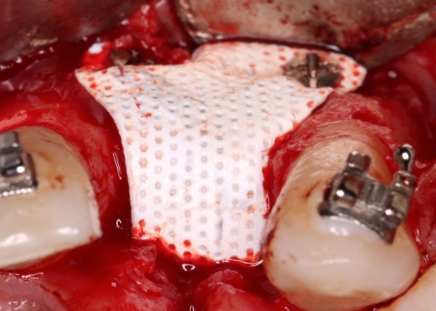

Foi estabelecido tratamento regenerativo prévio (Urban, 2013) (Fig.2/3) com membrana de PTFE-d (Cytoplast TXT250 Vestibular 17mm x 25mm) e posterior instalação de implante do tipo cone morse (Due Cone – Implacil De Bortoli) e tapa implante (Max Cover – 2mm), obedecendo todos os critérios de filosofia de tratamento para tal (Nentwig, 1987). Fig.4A/B

Fig. 2